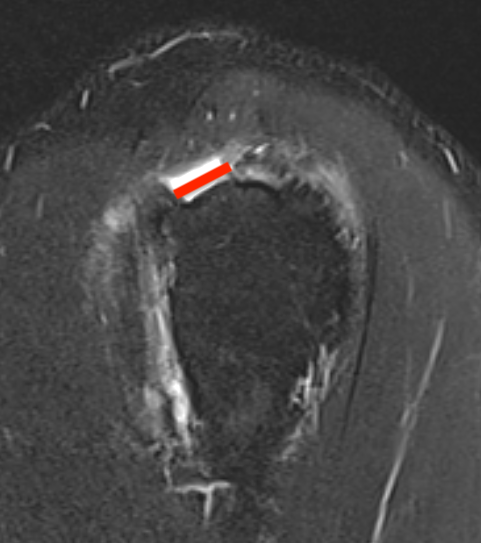

Full thickness rotator cuff tears

Partial bursal sided tear Partial articular sided tears

Small full thickness rotator cuff tear of supraspinatus - retracted to footprint

Large full thickness tear of supraspinatus and infraspinatus tendon - retracted to midhumeral head

Massive rotator cuff tear of the supraspinatus and infraspinatus tendon - retracted to glenoid